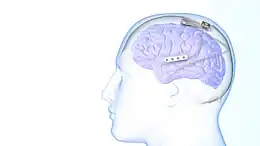

Responsive neurostimulation device is a medical device that senses changes in a person's body and uses neurostimulation to respond in the treatment of disease. The FDA has approved devices for use in the United States in the treatment of epileptic seizures[1] and chronic pain[2] conditions. Devices are being studied for use in the treatment of essential tremor,[3] Parkinson's disease,[4] Tourette's syndrome,[5] depression,[6] obesity,[7] and post-traumatic stress disorder.[8]

The use of neurostimulation to treat epileptic seizures is only recommended in those who have failed multiple medications for the treatment of their seizures. The NeuroPace RNS system was approved for use by the FDA in 2013 and is the only medical device for epilepsy that uses responsive neurostimulation.[1] The device is surgically implanted into the patient's head with electrical leads placed near the site in the brain that is believed to be the origin of the patient's seizures. These leads record electrical activity in the brain and deliver electrical stimulation when a seizure is detected.[9] The device keeps a record of abnormal electrical activity that is reviewed by a neurologist to improve the detection and treatment of seizures. The patient is able to record when they are having symptoms with the device to see if their symptoms are correlating with seizures.[1] The use of responsive stimulation has found to be effective for seizure reduction. Some patient's are able to achieve complete seizure freedom with responsive and non-responsive neurostimulation.[10]